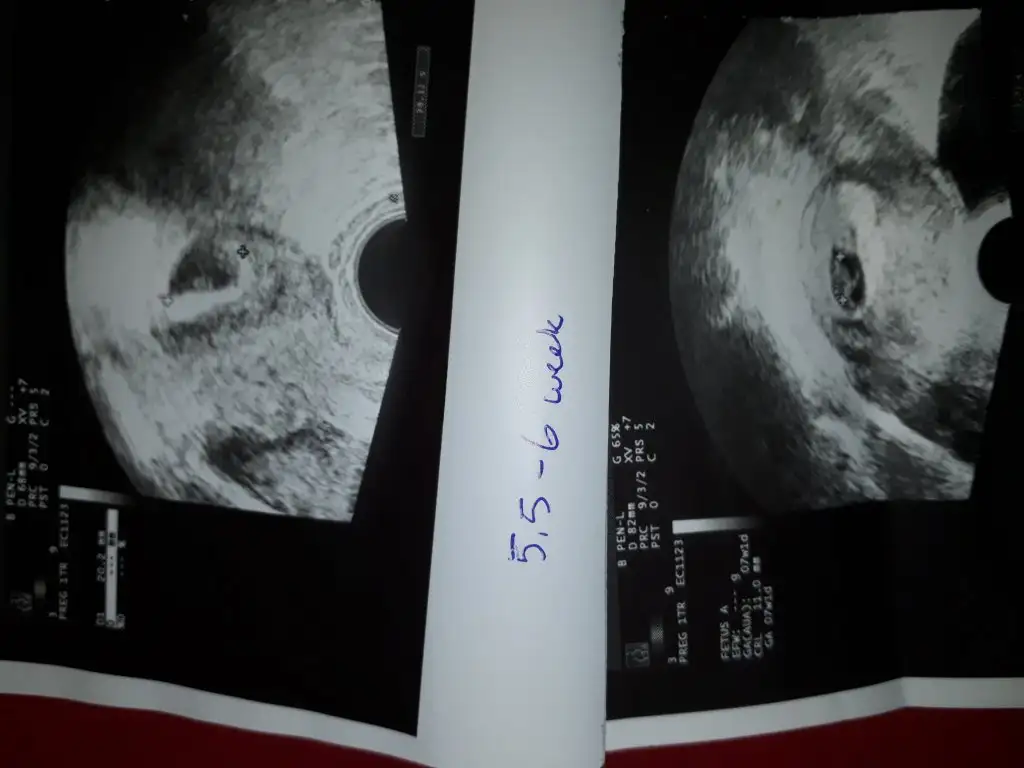

Kardesimin usg var bi bak istersen buna yorum yap .dikkatlice baktiginda gozukuyor .vajinal usg 5hafta

Bu benim 5.hafta vajinal ultrasonum ilk fotoğraftaki. altta 6. hafta diyor ama benim 1 hafta geç döllenme.